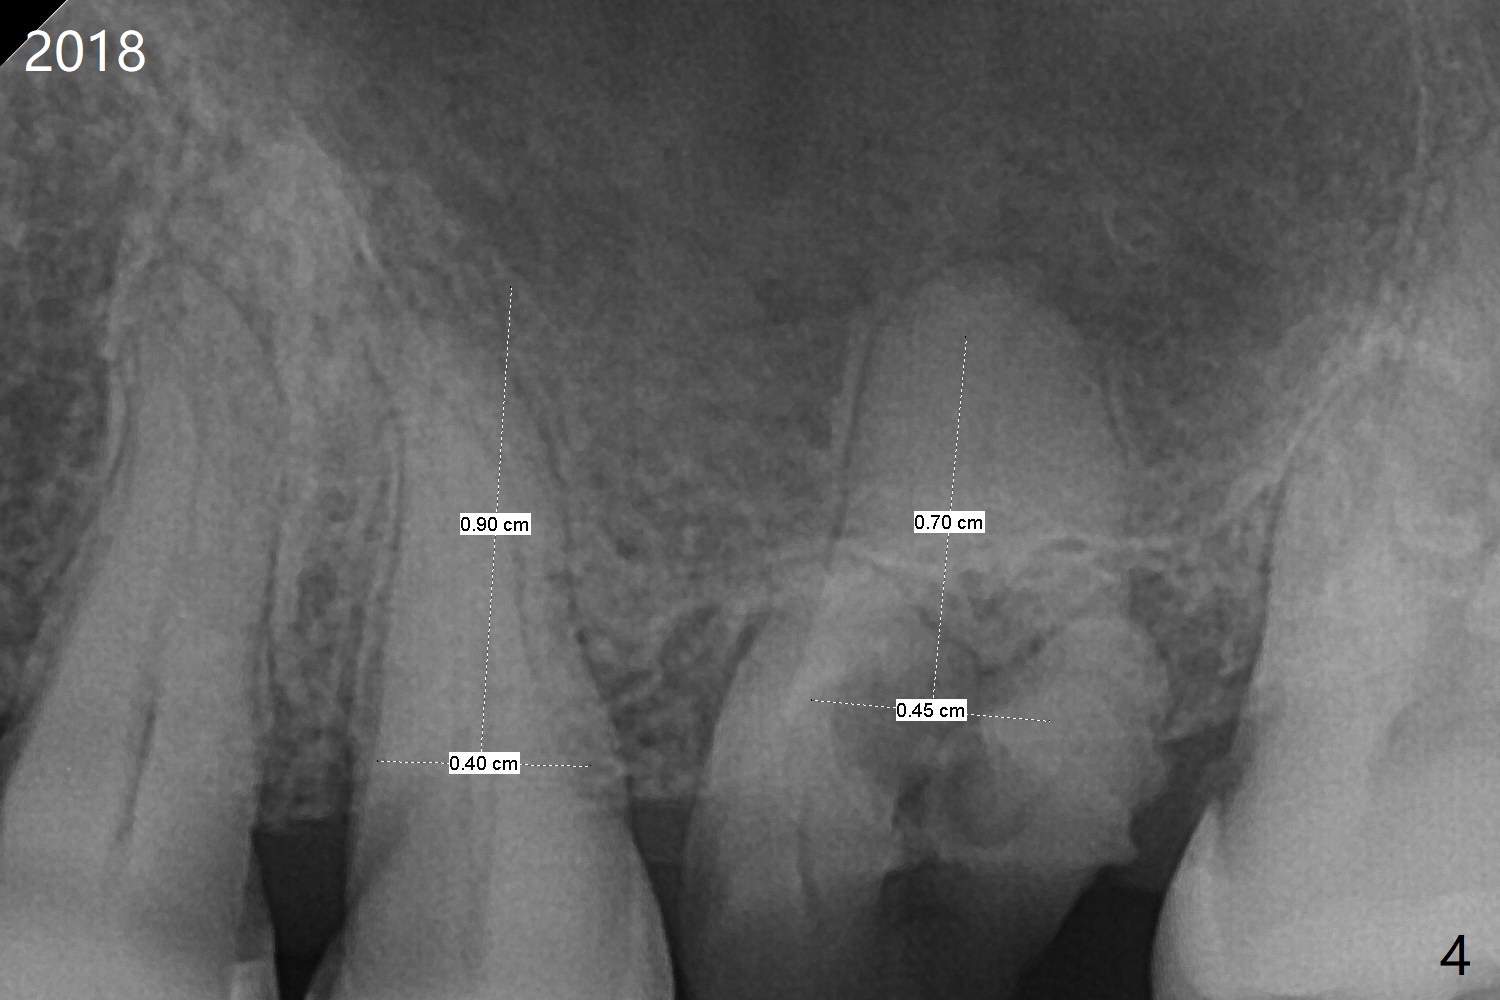

A 59-year-old nervous woman has poor dentition with upper left pain (Fig.1). Composite was placed at #12 and sedative filling at #13 two years ago. If the tooth #14 causes discomfort, it should be extracted for bone graft or immediate implant (Fig.4). PRF will be prepared (x2, white and red). The implant will be placed slightly palatal (P, Fig.2), since the residual buccal roots are more likely associated with buccal plate bone loss. If she agrees with treatment planning, take 5x5 cm CT for the bone loss and sinus. Sinus lift seems necessary because of short bone and septum (Fig.2,3).